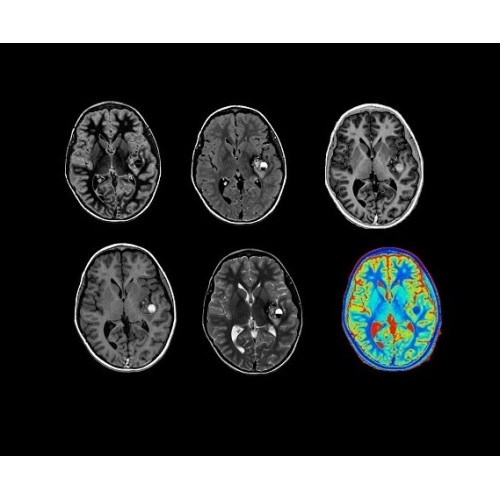

SIGNA Architect 3.0T — это новейший МРТ аппарат компании GE, который предлагает высочайший уровень производительности — в системе 128 приемных каналов, 48 канальная катушка головы, полный спектр клинических возможностей. Высокий уровень комфорта пациента обеспечивают такие особенности как отсоединяемый стол, положение пациента «ногами вперед» для всех видов исследований, SilentWorks — бесшумное и MAGIC — быстрое сканирование.

Теперь возможности МРТ поражают еще больше благодаря ультрасовременным решениям для визуализации с SIGNA Architect 3.0 Тл, объединяющей новейшие достижения в области МР-технологий и интуитивно понятный интерфейс. Система SIGNA Architect, разработанная на базе новой платформы SIGNA Works, представляет собой гармоничное сочетание дизайна и функциональности. Каждый элемент системы направлен на повышение производительности, эффективности клинической практики, финансовых показателей, а также комфорта и безопасности пациента.

Стандартный пакет приложений SIGNA Works позволит вам достичь желаемых результатов в клинической практике благодаря набору высокоэффективных средств визуализации. Программные приложения, входящие в состав данных клинических пакетов, включают широкий спектр контрастов, функции обработки 2D- и 3D-данных, а также возможность коррекции артефактов движения. SIGNA Works предоставляет набор инструментов, необходимых для проведения эффективного клинического исследования.

• NeuroWorks — универсальное решение для визуализации анатомии головного мозга, позвоночника, сосудов и периферических нервов с четкой дифференциацией тканей.